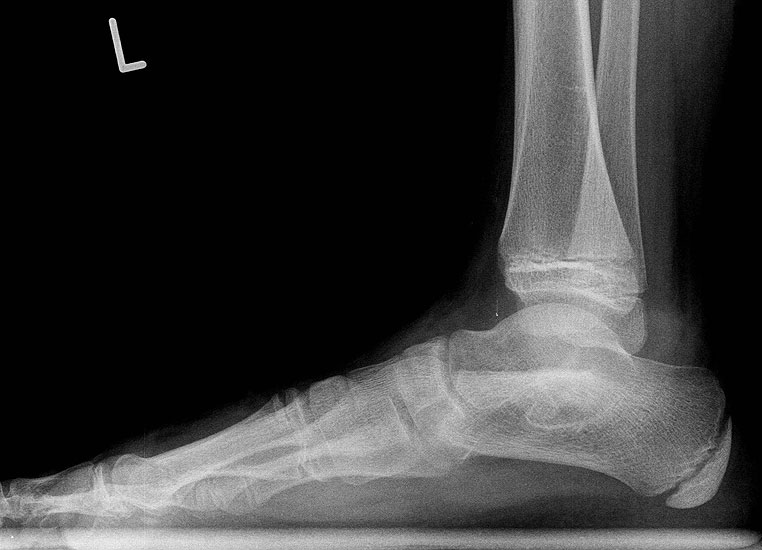

Z.n. Distorsion des Fußes mit „Ruptur“ der (vorbestehenden) talocalcanearen Coalitio. Die Wassereinlagerung in den an die Coalitio angrenzenden knöchernen Bezirken ist im MRT gut zu erkennen. Nach monatelangen Beschwerden spontane Besserung.

Abbildung 1

• Anhaltende Schmerzen nach vermeintlichen oder tatsächlichen Distorsionen („Aktivierung“ der Coalitio, vgl. Abb. 1)